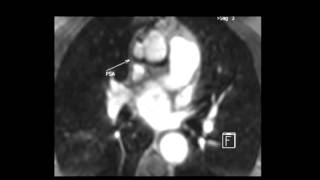

Single Stage Correction of Ascending Aortic Aneurysm and Coarctation of Aorta- CT Images.